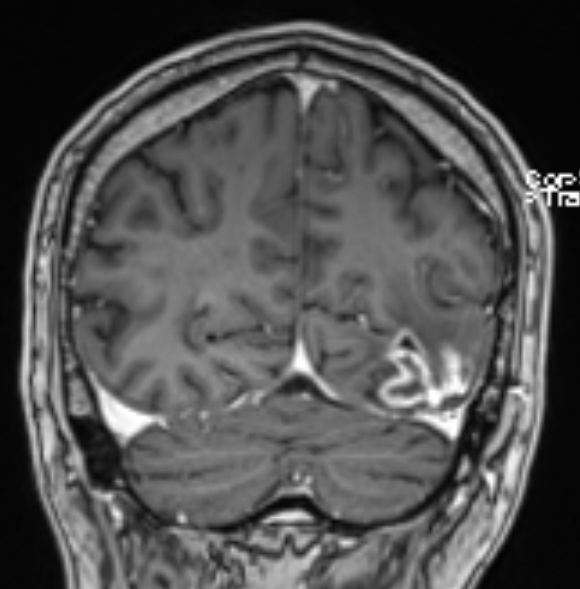

• 54-jähriger Mann, der vor 4 Jahren ein Adenokarzinom des rechten Lungenoberlappens cT4 cN1 M0 entwickelte

•  Cisplatin / Alimta - Chemotherapie, dann Radio –Chemotherapie 50Gy, 3 Zyklen simultan Cisplatin und Pemetrexed

• extrapleurale Oberlappenresektion,  Lymphadenektomie

• postoperatives Stadium ypT3 ypN0 L0 V0 G3

• adjuvante Bestrahlung der Thoraxwand rechts ED 3 Gy, GD 30 Gy

• vor 2 Jahren Metastase links parieto – occipital,  neurochirurgische Entfernung, Bestrahlung des Neurokraniums mit 30 Gy, ED 3 Gy

• vor 1 Jahr  Exstirpation einer Hirnmetaste links occipital, Bestrahlung des Hirnmetastasenbettes links occipital mit 40 Gy, ED 2 Gy

Die linke Spalte zeigt MRTs vor 7 Monaten, die rechte Spalte aktuelle MRTs.

Die MRTs zeigen eine Zunahme der Gadolinium-anreichernden Bezirke. Die Exzision erbrachte Großhirngewebe mit Anteilen einer Nekrose. Kein Tumorgewebe.